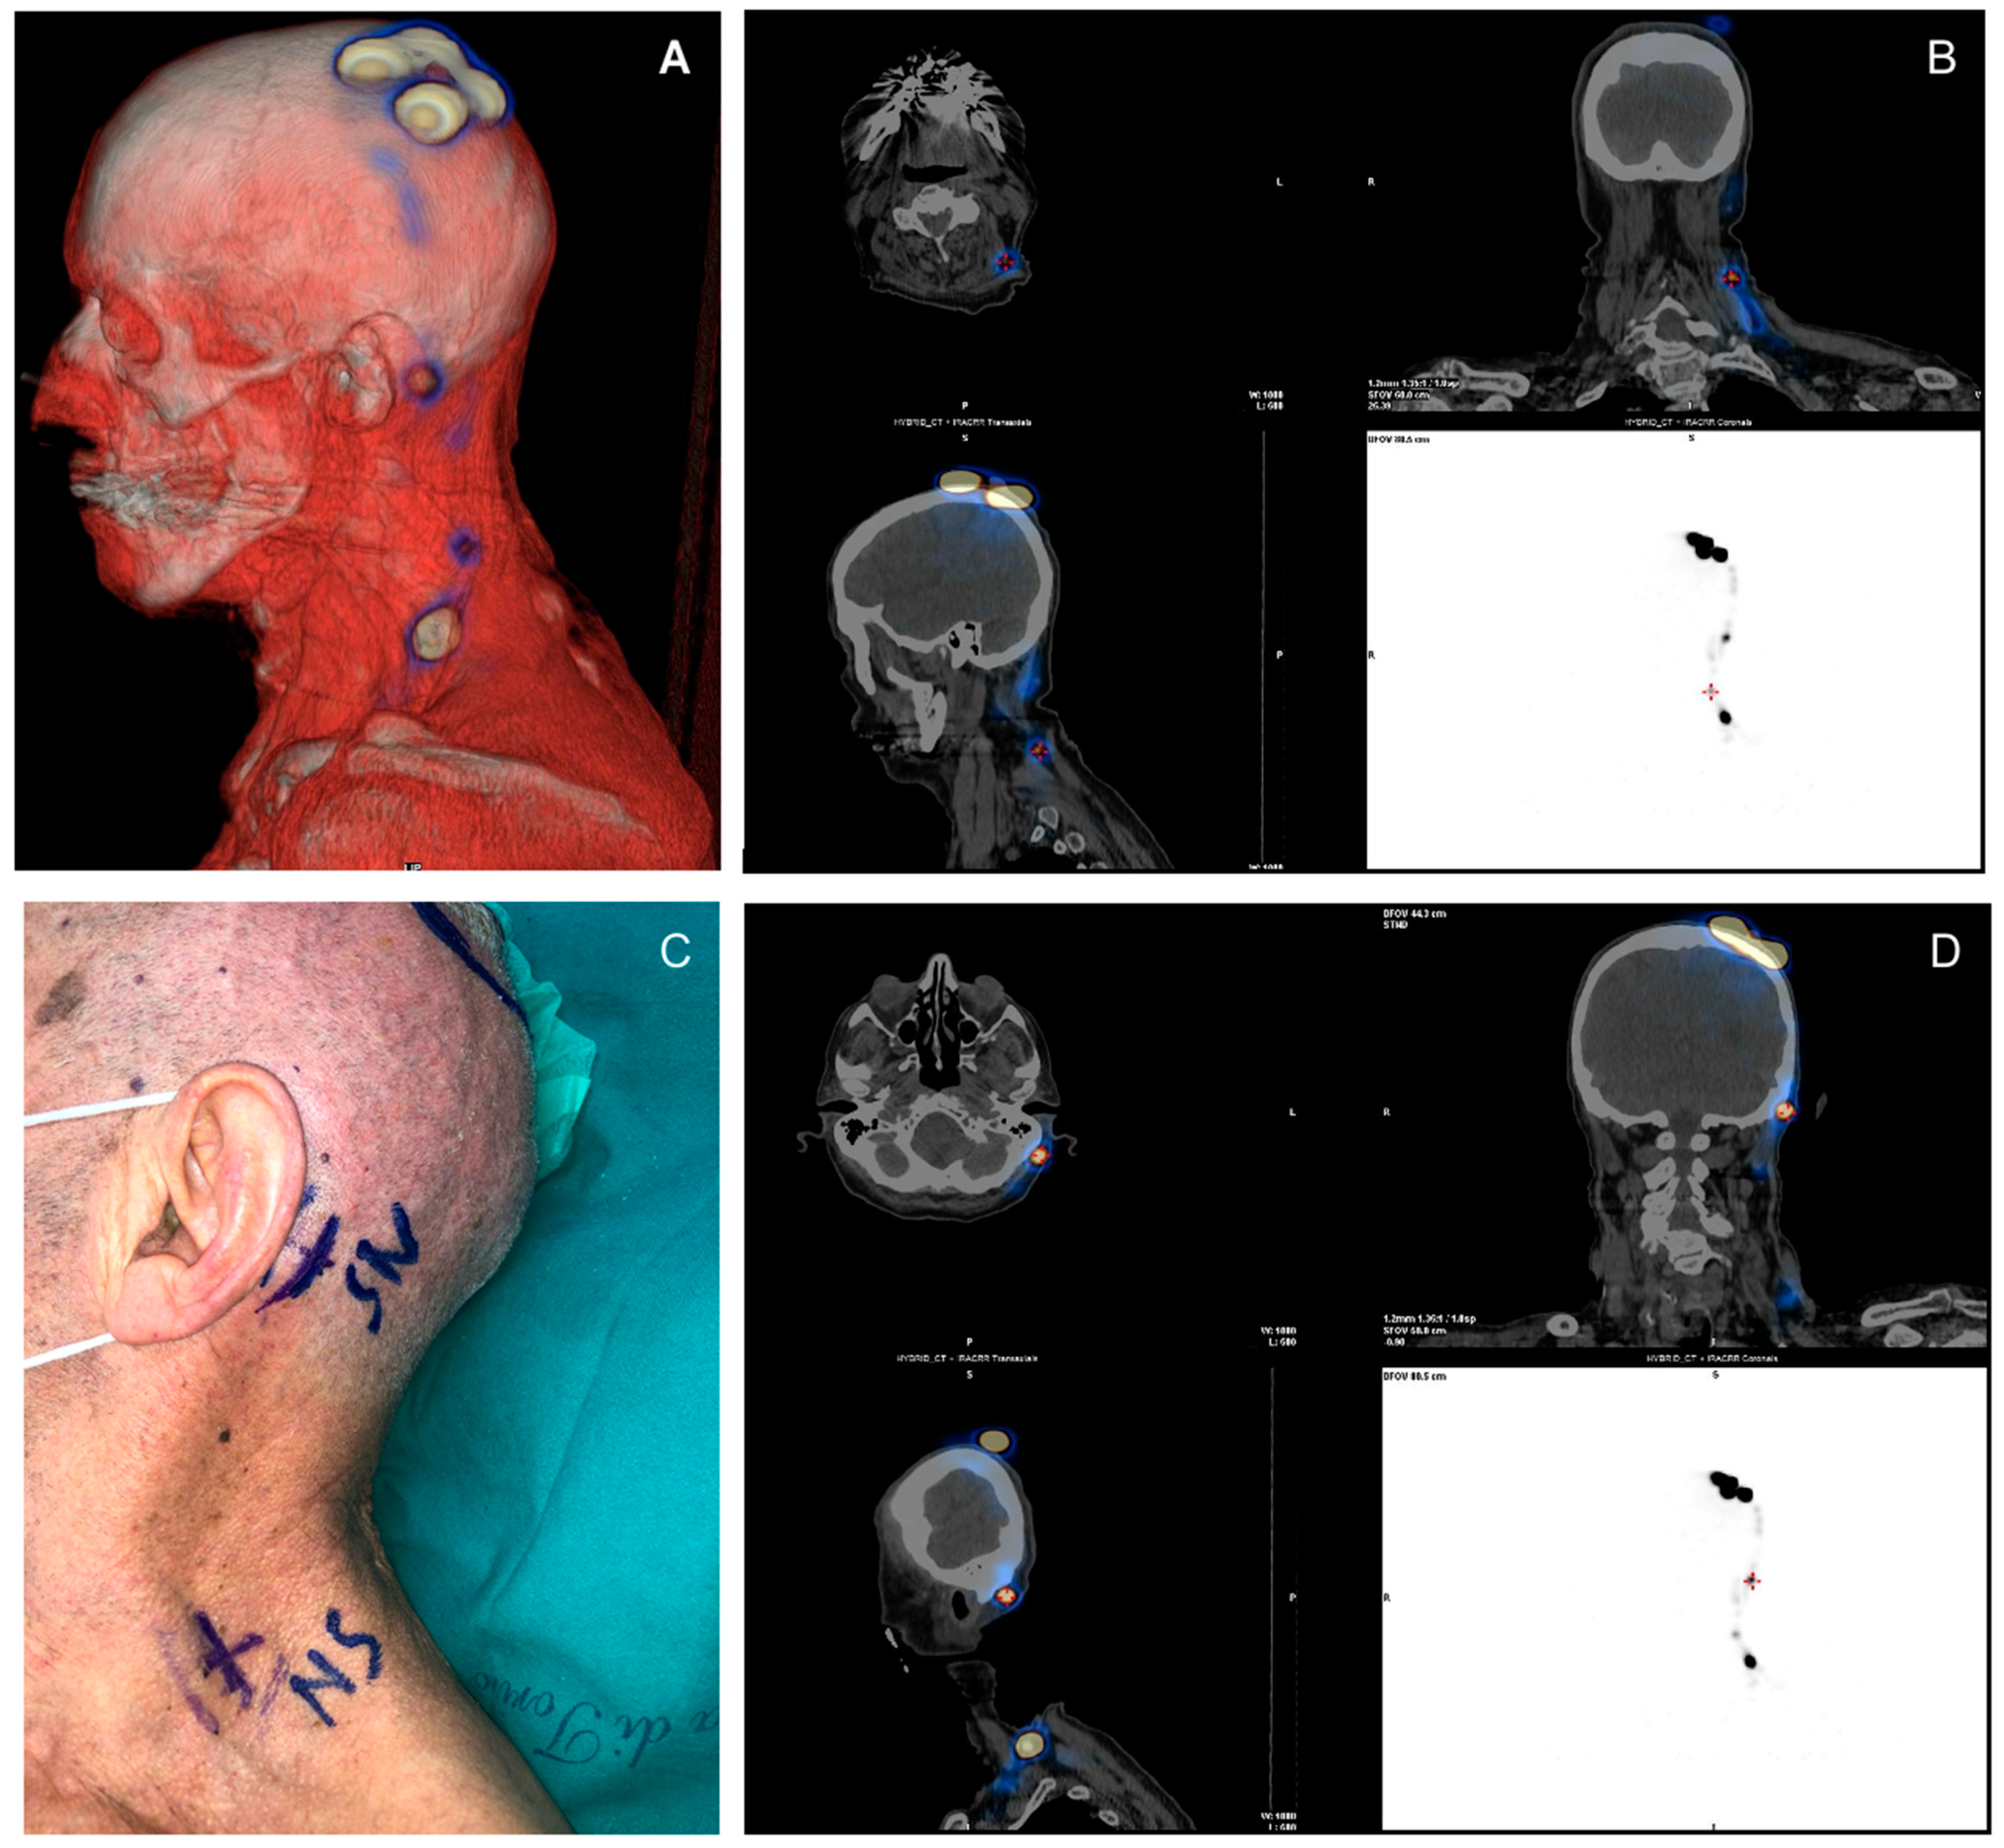

SPECT-CT Technique

3.2. SPECT-CT